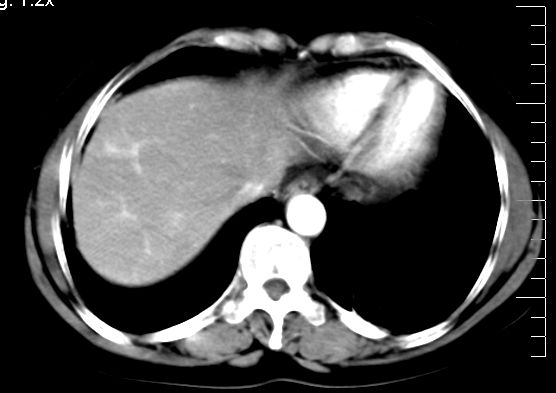

标题: CT10752:F,52岁,反复上腹部疼痛,平扫+增强. [打印本页]

f、52岁,反复上腹部疼痛2年。肺结核病史10多年,胸片双上肺结核纤维化。

ct表现:

肝大小形态未见异常,肝内外胆管无扩张,肝s8段见一动脉期明显血管样强化结节,门脉期呈高密度,延迟期呈等密度,胆囊不大,增强扫描见胆囊及胆囊颈管壁增厚,有强化。

诊断:

1、胆囊炎(轻度)。

2、肝s8段结节,考虑小血管瘤。

4、目前ct表现尚不能解释患者上腹部疼痛,建议上消造影检查,除外胃炎等疾患。

肝右上叶血管瘤!

考虑肝右叶前上段包膜下小血管瘤。

支持肝右前叶上段小血管瘤

肝上近膈顶小血管瘤